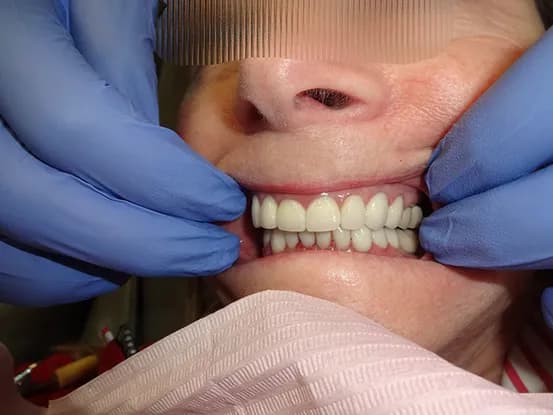

Case 5

54 year old female with 2 mm opened anterior bite, staining and attrition. Bite cannot be closed to optimal position due to limitations of past orthodontic treatment. 10 upper e-max veneers were placed to optimize position, shape, color of upper teeth resulting in much improved cosmetics.